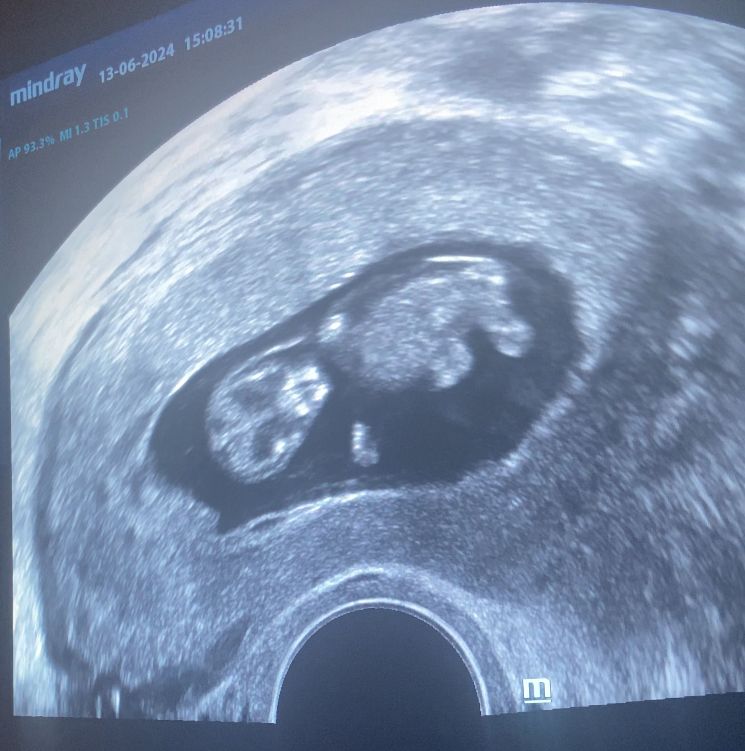

Узи в 10 недель 🤰🏻

Сегодня по сроку 10 недель, 3 дня

Такой уже маленький человечек внутри, махал нам ручками, ножками, копошился в своем домике 🥹

Ктр 34 мм

ПЯ 48 мм

ЖМ 5 мм